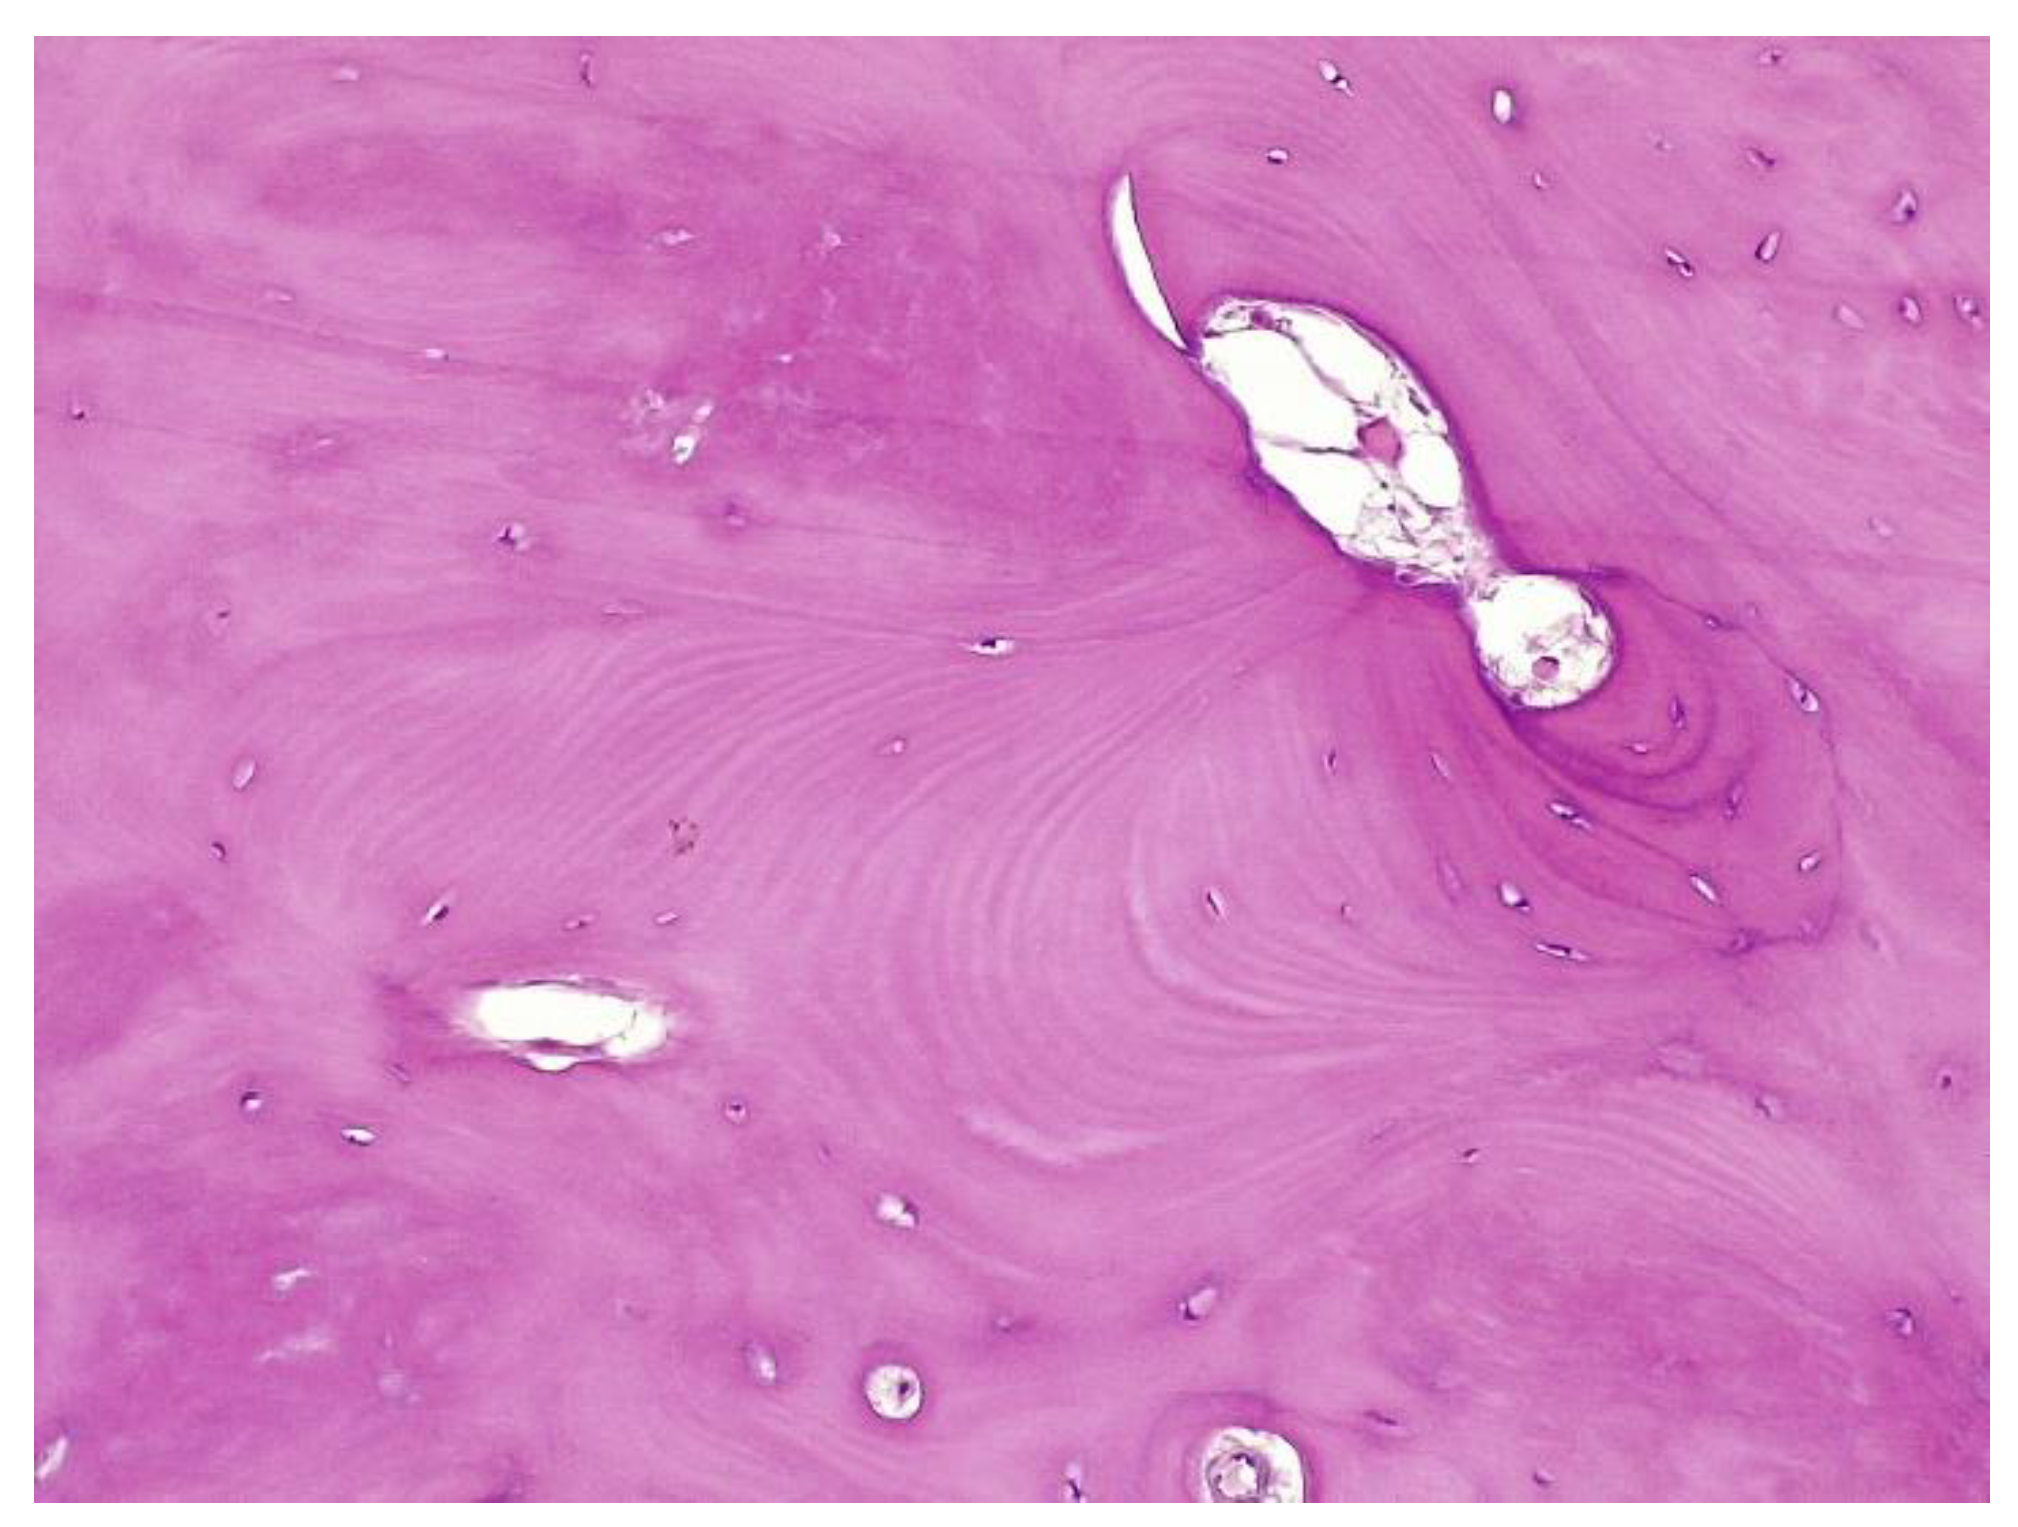

The histopathological result supported the diagnosis of melorheostosis (Figure 5, Figure 6, Figure 7 and Figure 8). Additionally, immunohistochemical tests completed the data obtained after the microscopic examination through the classic histopathological technique. CD45/LCA (clone PD7/26/16 and 2B11, Biocare) demonstrated the presence of inflammatory cells, but overall, the rest of the immunohistochemical tests were non-specific and did not reveal the presence of epithelial or other tumor proliferations on the analyzed specimens. CD138 (clone B-A38, Biocare) showed rare plasma cells dispersed in hematoforming marrow, CD56 (clone BC56C04, Biocare) highlighted few osteoblasts, and all specific immunomarkers for cytokeratins were negative (Pan Cytokeratin AE1/AE3 clone AE1/AE3 and CK8/18 clone CK8/18 both from Biocare). Ki67 (clone SP6, Biocare) was negative in areas of reactive fibrosis and positive in a few cells in the hematoform marrow, suggesting a benign lesion. CD56 usually highlights neuroendocrine tumors, myeloma, myeloid leukemia, and Nk/T cell lymphomas and is also positive in some rare sarcomas. The negative panCK marker denied the possible epithelial tumor origin. Although there are no specific immunomarkers for this pathological entity, there are some studies that try to find correlations between the immunohistochemical expression of some proteins and the severity of the lesions. One study used immunohistochemistry to investigate the expression of several proteins in the affected bone tissues of melorheostosis patients. The study found that there was increased expression of certain proteins, including transforming growth factor beta (TGF-β), bone morphogenetic protein 2 (BMP-2), and insulin-like growth factor 1 (IGF-1) in the bone tissues of melorheostosis patients compared to healthy controls [8].

The histopathological appearance varies, but several pathognomonic changes have been identified, such as increased bone cortical density, the presence of woven bone features, hypervascular features, an increased number of Haversian systems, and irregular bone growth into the medullary cavity; moreover, newly deposited unmineralized osteoids were seen in affected lesions [23].

Figure 5. Marked endosteal sclerosis with marrow fibrosis.

Figure 6. Abnormal proliferation of thickened compact, haversian, or woven bone distorting the normal smooth contour of the periosteal surface of the bone.

Figure 7. Remarkably dense compact bone with no significant architectural alteration, consistent with melorheostosis.

Figure 8. The osseous nodule consisted of mildly hypercellular compact lamellar bone with slightly irregular cement lines.